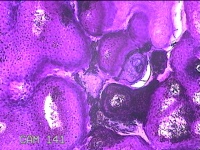

骶尾部皮肤结节

性别

男

年龄

39岁

临床诊断

皮下结节

一般病史

发现骶尾部皮肤结节2年余。

标本名称

大体所见

灰白粉红色组织2.3x1.7x0.3cm一块,表面带梭形皮肤2x1.3cm,皮下见结节1.8x1.2cm一个,切开结节呈囊性,囊内充满大量灰白色角化物,囊壁厚0.1cm。

图3